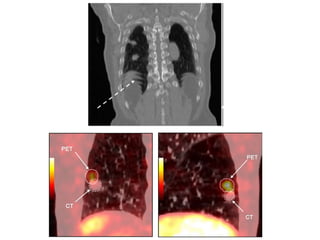

Need for gating

• CT acquisition will be fast. Cycle that will be

captured depends on the respiratory cycle.

• PET CT is acquired in free breathing.

• Normal cycle: Expiration > Inspiration.

• PET images of thorax mostly represents data

of end expiration.

• Problems with attenuation and scatter

correction.

• Problems with localisation.

• Partial volume effect.

• Affects the quantification- importantly MTV